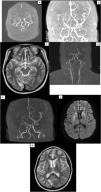

ResultsThere are 58,905 unique MRI scans from 2019 to 2023. The cohort comprises 8 females and 2 males, with a median age of 37 (7–65) years old. Three cases are probable MMD. with six MMD cases and one MMS case. Therefore, the prevalence rate for the four years is approximately 11.9 cases per 100,000 scans. Out of the confirmed Moya-Moya cases, the majority (4/7) are ischemic subtypes, followed by epileptic (electroencephalography shows slowing brain waves) and TIA in one case each. The most common presenting symptom is weakness in the extremity (N = 7), followed by headache (N = 5). Four patients underwent operative procedures, with three of them being superior temporal artery to middle cerebral artery (STA-MCA) bypass procedures and one of them being encephalo-duro-myo-arterio-pericraniosynangiosis (EDMAPS).